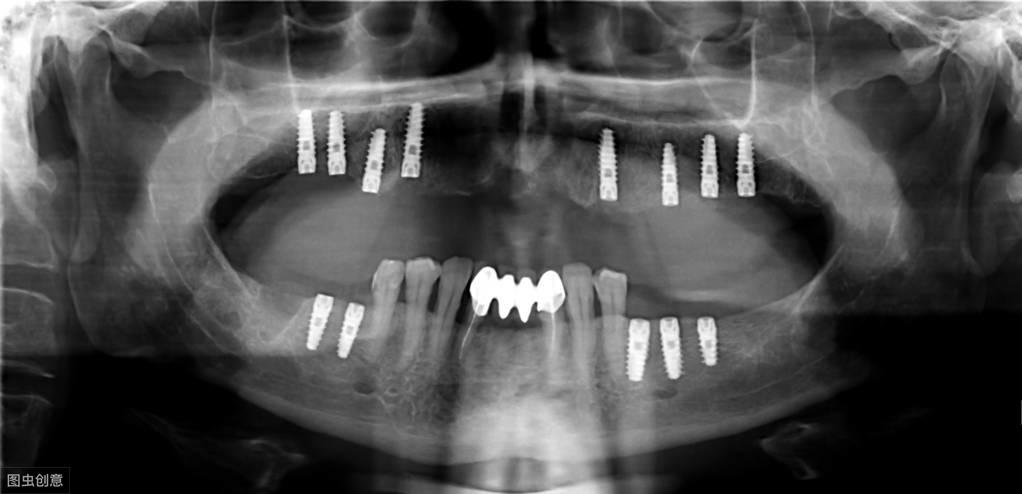

種植牙手術(shù)示意圖

種植牙技術(shù)是近幾十年出現(xiàn)在大眾視野中的一種修復(fù)缺失牙體的方法。一顆完整的種植牙體由三部分組成:種植體、基臺(tái)、人工牙冠。

手術(shù)過(guò)程就是將種植體植入患者的牙體缺失處,待其傷口愈合,種植體與牙槽骨結(jié)合牢固后,將基臺(tái)安裝在種植體上,再將人工牙冠安裝在基臺(tái)上,形成完整而堅(jiān)固的人工牙體。